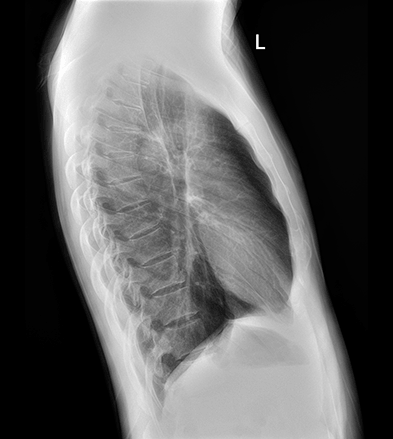

临床图像